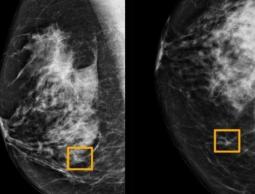

كما أطلقت شركة الأدوية BioScent Dx دراسة حول ما إذا يمكن استخدام الطريقة ذاتها للكشف عن سرطان الثدي، كما سيتم إجراء المزيد من الأبحاث لتحديد المكونات الكيميائية في عينات الدم التي تسبب الرائحة وتمكن الكلاب من شمها واكتشافها.